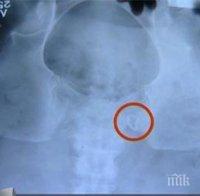

Личният лекар на Траяна я посъветвал да отиде на скенер, за да разберат какво ѝ причинява непоносимите болки. Апаратът показал, че в тялото ѝ има забравена макара. Въпреки уверенията на хирурзите, че това е невъзможно и всичко с повторната операция е наред, болките на Траяна ставали все по-нетърпими.

Жертвата на двойната лекарска грешка потърсила второ мнение в друга болница и след много ехографии и рентгенови снимки лъсна истината, че в тялото ѝ има чуждо тяло с размер 35-40 мм.